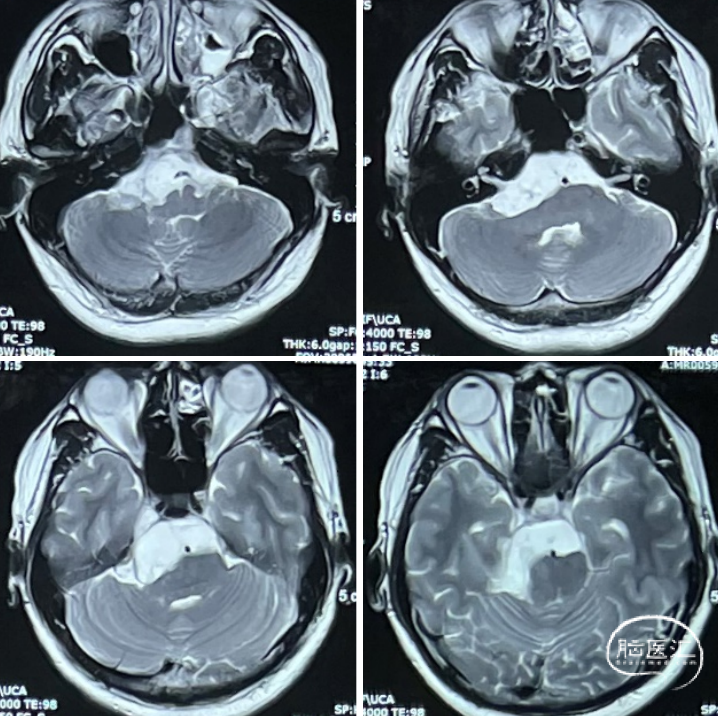

术后MRI